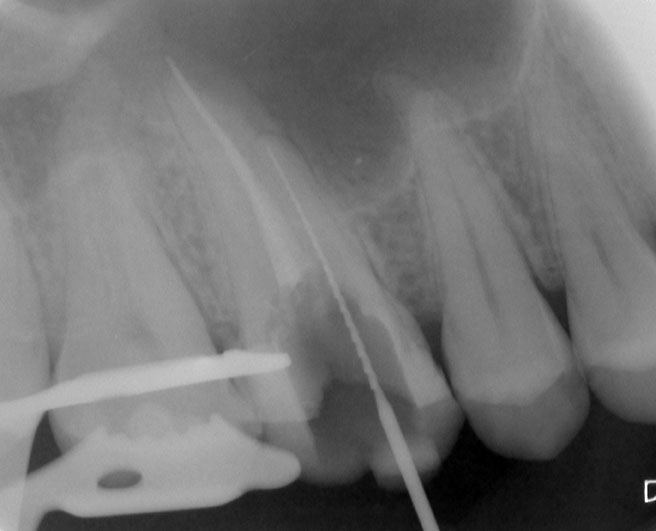

Nach Darstellung aller Wurzelkanaleingänge wird in einem zweiten Schritt das frakturierte Wurzelkanalinstrument dargestellt (Abb. 3 u. 4). Hierfür verwenden wir den Aufsatz 3E des Tigon+. Durch die schmale und lange Form des Instruments erreichen wir einen tiefen und schmalen Zugang.

Abb. 3 u. 4: Zustand nach Revision des Wurzelkanals und Darstellung des frakturierten Instruments.

Sofern es sich um ein kleines Frakturstück handelt, kann es durch aktive Übertragung von Energie des Ultraschalls zu einer Lockerung des Fragments kommen. Lockert es sich nicht, so „umkreist“ man das Instrument vorsichtig, um es anschließend mit einer Spritze gefüllt mit Palavit G zu greifen, zu fixieren und zu entfernen (Abb. 5). Nach Entfernung des Instruments erfolgt eine Kontrollaufnahme (Abb. 6).